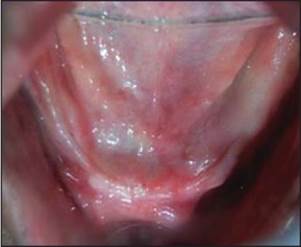

Se planificó un protocolo quirúrgico de dos etapas y se le pidió al paciente que tomara antibióticos y analgésicos antes de la cirugía. El colgajo mucoperióstico se elevó por todo el maxilar superior y la plantilla se colocó en la cresta de la cresta con broca piloto se lleva a cabo [Figura 4] y [Figura 5] . Se colocan herramientas paralelas y se verifican las angulaciones del implante. Se utilizaron taladros secuenciales y se colocaron implantes en el sitio de osteotomía y se introdujeron en el sitio hasta que se enterraron todos los hilos. Se colocaron tornillos de cubierta y se realizó la sutura [Figura 6]. La atención postoperatoria se ha administrado con antibióticos, analgésicos y enjuagues bucales. Se sugirió mantener la higiene bucal y la compresa de hielo si fuera necesario. Se siguió un procedimiento similar para la mandíbula y se realizó la sutura [Figura 7] . Después de 3 meses, el paciente fue retirado del mercado y se realizó una OPG postoperatoria y se verificó su adecuada osteointegración. Después de confirmar la osteointegración, el colgajo se elevó y se retiraron los tornillos de cobertura y se colocó por extensión de la mucosa y esperó durante una semana para que se produzca la curación (Adell R, etal., 1981) [Figura 8] .

Después de la curación, se eliminaron las extensiones por mucosa y se colocaron análogos de impresión. La impresión de bandeja abierta se realizó con material de impresión elastomérico y se aflojaron los análogos de impresión. El análogo de implante se roscó al análogo de impresión en la bandeja de impresión y se vertió el molde. Se colocó el pilar sobre el yeso y se realizó el montaje. Se llevó a cabo una prueba con metal, luego se realizó la acumulación de cerámica y se fabricó la prótesis final y se verificó en la cavidad oral y se realizó la cementación final [Figura 9] . Las instrucciones de higiene oral postoperatorias se dieron al paciente y se realizó un seguimiento adecuado (Kim, Misch y Wang, 2005).

Figura 9. Prótesis final